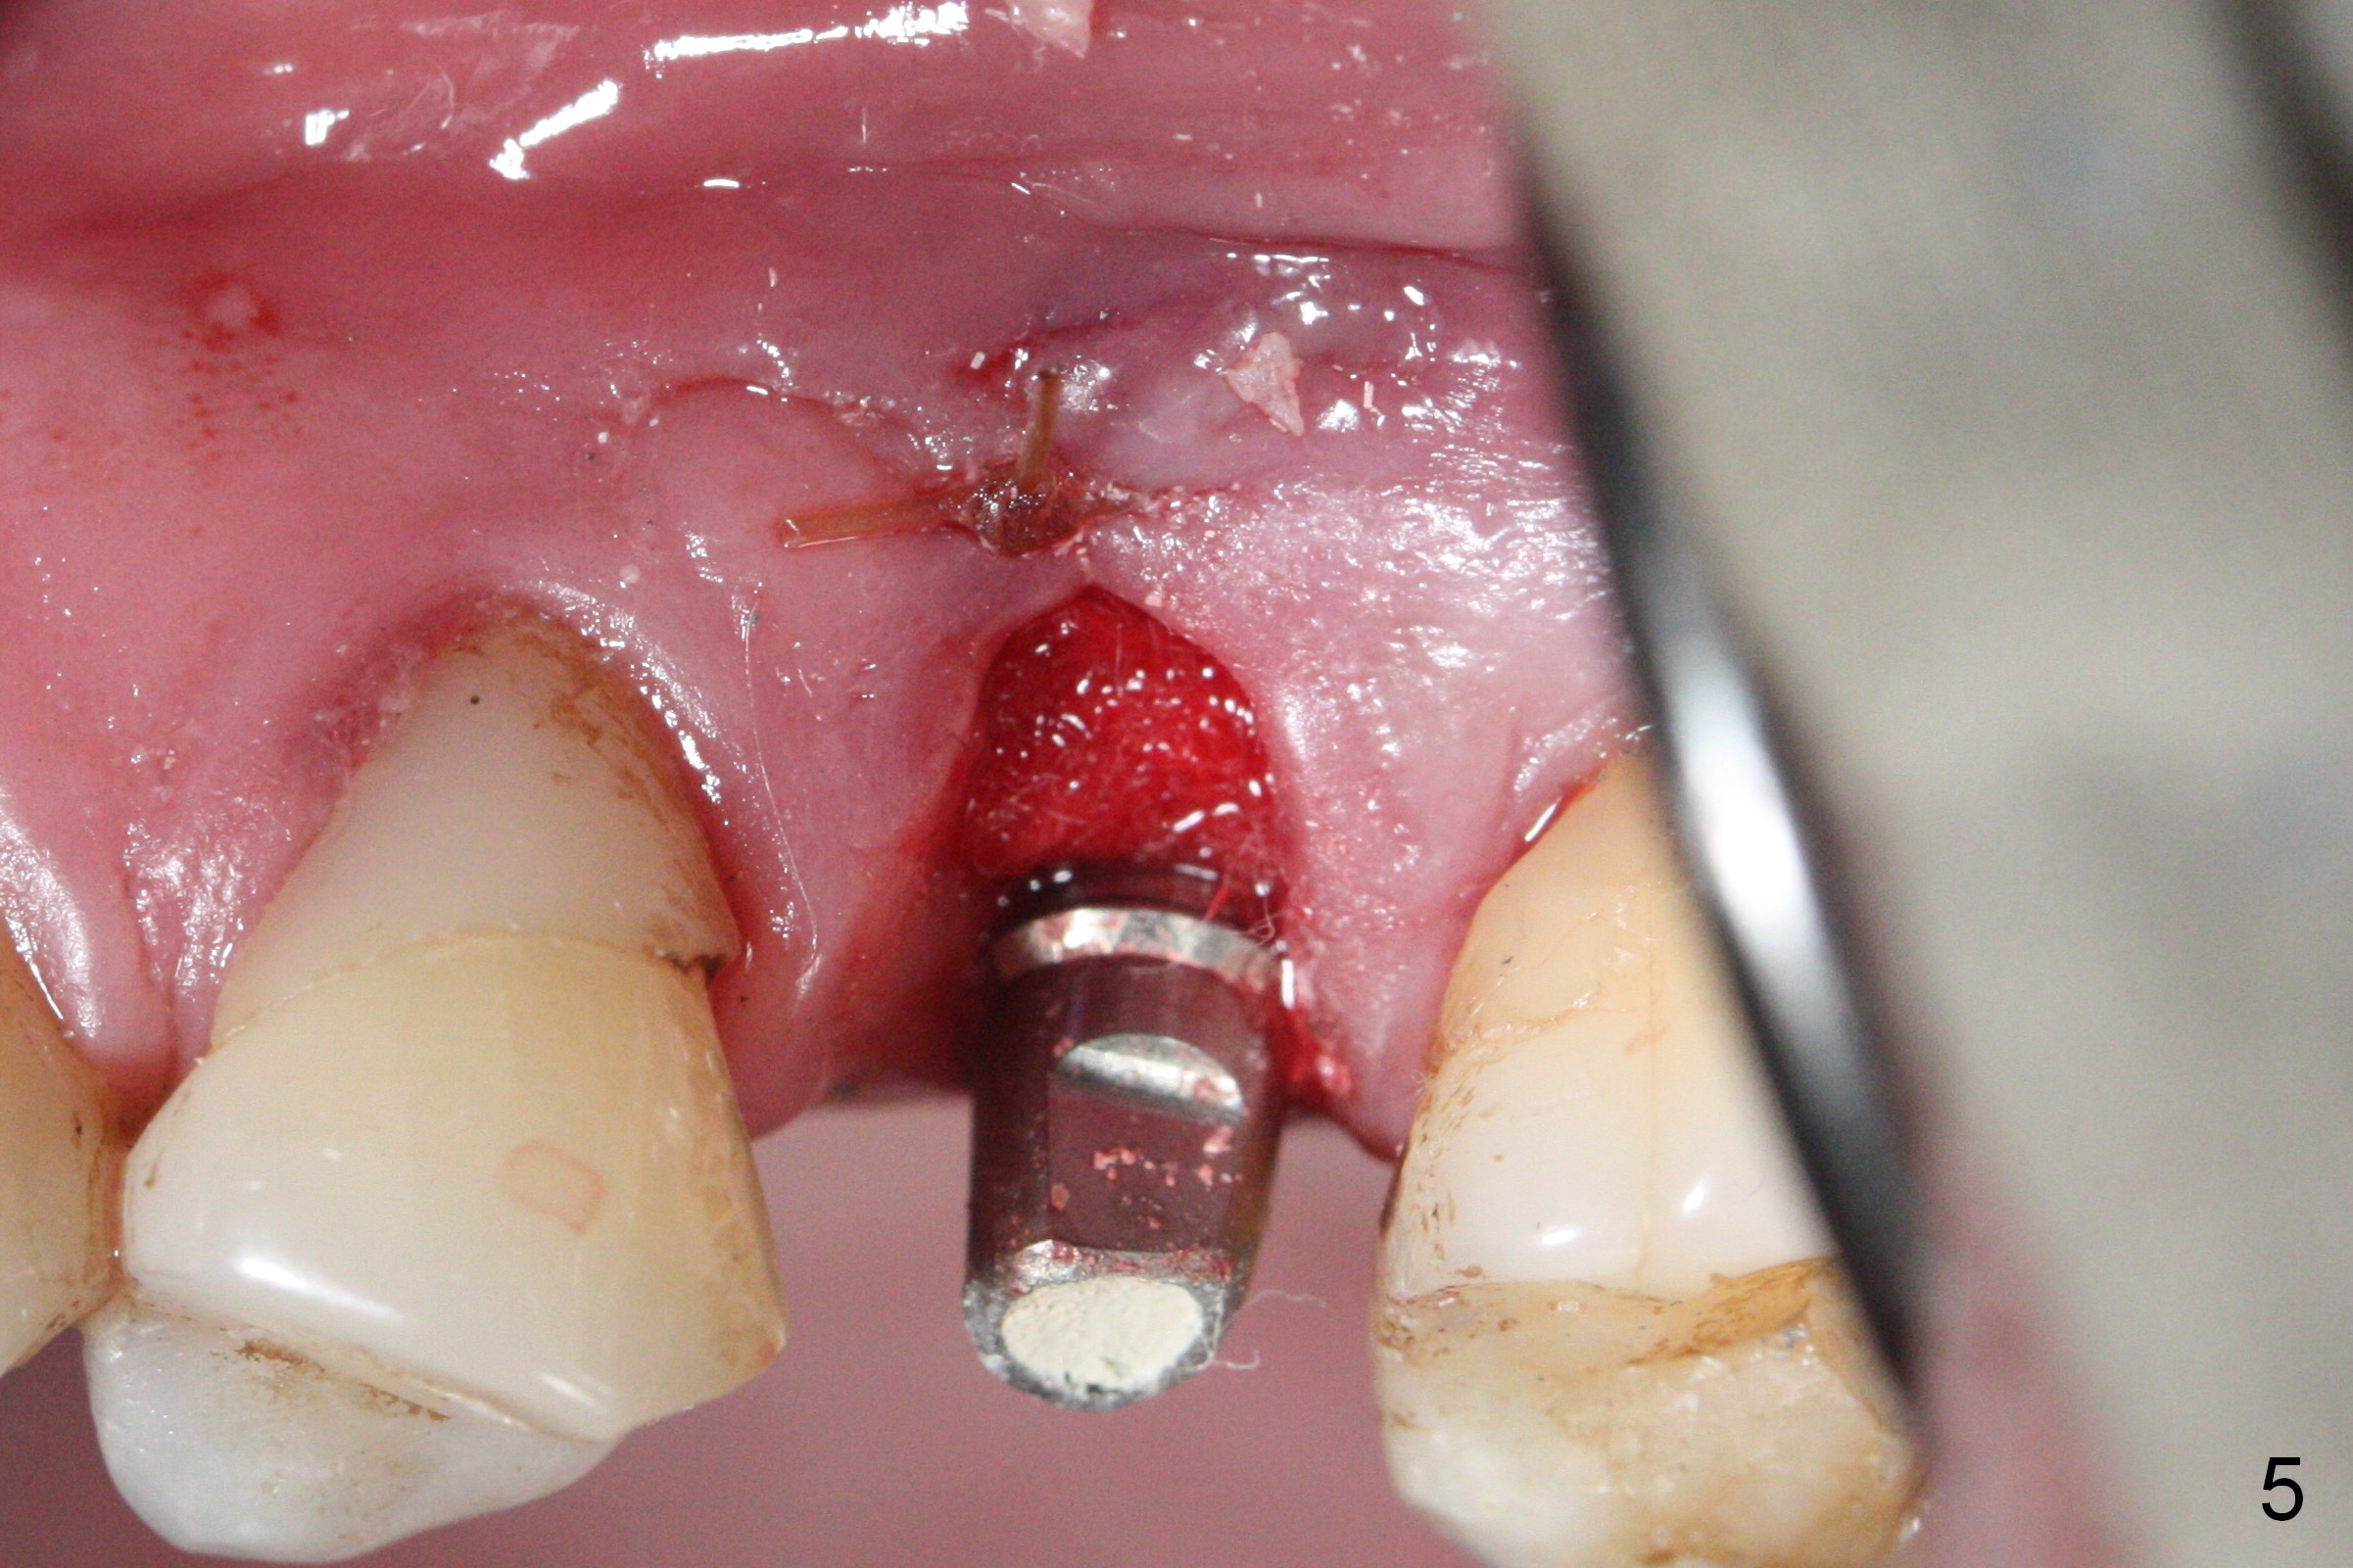

When the fractured root from the smoke-reducing patient is being removed by a root tip pick, the buccal gingiva is lacerated, partially due to loss of the buccal plate. Later suturing is required (Fig.5).

Initial osteotomy depth is 18 mm (Fig.1 green line) with 9 mm in the native bone (red line). The bone density feels to be low. There is at least 2 more mm bone apically (pink line). The depth is increased by 2 mm so that when a 3.8x15 mm implant is placed, there is 10-11 mm implant/bone contact (Fig.2 red line). There is large bony defect (Fig.3 *), which is bone grafted (Fig.4 *). Finally a longer abutment is placed (4.5x5.5(5) in Fig.4 vs. 4.5x4(5) in Fig.2,3). The 5 mm cuff does not look too long buccally (Fig.5) or palatally (Fig.6). To prevent postop buccal gingival overgrowth (2), the buccal margin of an immediate provisional is subgingival (Fig.7-9 *). Bone density between #13 and 14 appears to increase 3 months postop (Fig.10). The implant seems to be equi-crestal (Fig.11 ^). There seems to be more bone growth (i.e., decreasing gap) 6 months postop (Fig.12). Impression is taken. A crown is delivered nearly 7 months postop (08/07/2017). While there is minimal bone loss at #13 and 15 three years and 4 months post cementation, the tooth #14 and 18 are mobile (Fig.13,14).